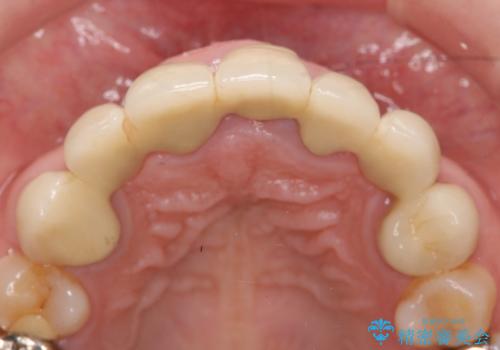

- 昔治療した前歯の被せ物の見た目を改善したいといらっしゃった方の症例です。

左上4番目の歯から右上3番目の歯まで計7歯のクラウンを除去し、オールセラミッククラウンによる補綴を行いました。

今回用いたオールセラミッククラウンはジルコニアフレームという白い素材の上にセラミックを盛っているため、審美性が非常に高いのが特徴です。

また、ジルコニアは人工ダイヤモンドの材料にも使われているほど高い強度を持っており、そのためオールセラミッククラウンは審美性だけでなく、奥歯やブリッジの補綴も可能とするクラウンです。